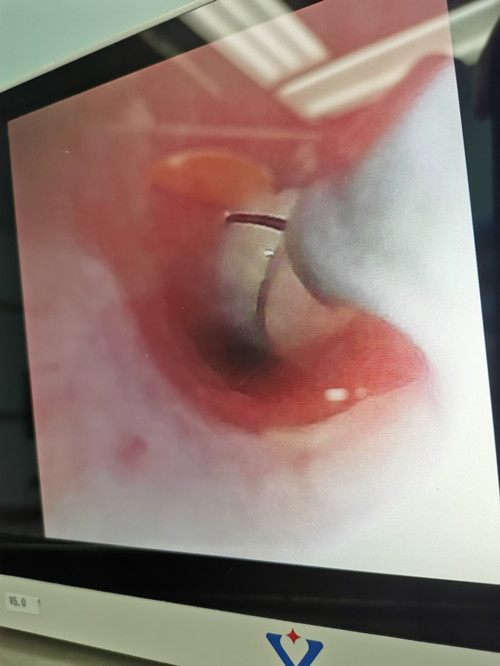

近日,儿科PICU医护人员运用气管镜下异物取出术,及时救治了一名因吃花生时哭闹、致气管内异物吸入的两岁患儿。

据了解,患儿前一日在家吃碎掉的花生时不甚摔倒,哭闹后出现呛咳、面部憋红、吼喘,被家属紧急送入我院抢救,查胸部CT显示其左主支气管异物。此刻患儿的病情风险大、难度高,但PICU的医护人员毫无畏惧,在取得家长的同意后,立即联系了医院手术室开通绿色通道,为患儿实施了全麻下的气管镜下异物取出术。因在疫情的特殊时期,医护人员操作时需要严格按照三级防护的要求穿上厚重的防护用具,无疑给操作增加了难度。再加上患儿年龄小,肺部空间非常狭窄,要反复调整气管镜的位置,旋转到合适的角度才能找到异物,且在钳取过程中异物很容易再次滑落进小气道,导致小气道堵塞更难钳取。面对重重困难,PICU医护人员齐心协力、相互配合,历时一个多小时,终于成功取出了这颗隐藏在很深位置、非常刁钻的花生,后用温生理盐水反复灌洗,将患儿气管里的堵塞物全部清理了出来。术后患儿病情明显好转,将于近期出院。